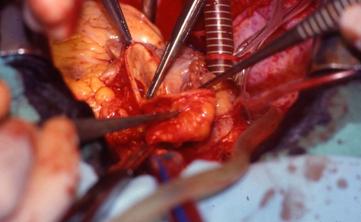

FOTO INTRAOPERATORIA - ANASTOMOSI VASCOLARE

Con questa tecnica vengono asportati completamente i due atri del ricevente. Le connessioni venose sistemiche sono effettuate a livello delle vene cave, mentre le connessioni venose polmonari vengono realizzate selettivamente con il cappuccio atriale separato dalle vene polmonari destre e dalle vene polmonari sinistre.

La fase di impianto prevede inizialmente l'anastomosi della cuffia atriale sinistra, come per la tecnica di Shumway, mentre le anastomosi successive, eseguite in termino-terminale, sono effettuate in questa successione: vena cava inferiore, vena cava superiore, arteria polmonare, aorta.